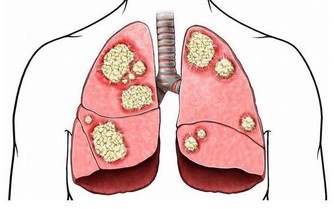

2. 肺:

理論上肺從20 歲就開始衰老。有些人到了40 歲,會開始氣喘吁籲。

這是因為控制呼吸的肌肉和胸腔變得僵硬起來,使呼吸相對於從前困難一些。